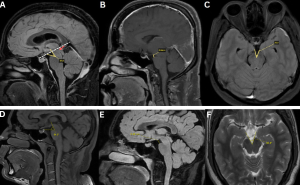

Quantitative signs (9).

- Reduced pontomesencephalic angle (<50°)

- Decreased mammillopontine distance (<6.5 mm)

- Narrowed interpeduncular angle (<40.5°)

- Inferior displacement of the cerebral aqueduct (iter) below the incisural line

Fig 7: Figure A: Measurement of the pontomesencephalic angle, defined as the angle between a line along the anterior margin of the midbrain and a line along the anterosuperior margin of the pons. A reduced angle (<50°) is indicative of downward brain displacement. An incisural line (drawn from the tuberculum sellae to the straight sinus confluence) demonstrates inferior displacement of the cerebral aqueduct/iter (red arrow) below this line (white dotted line).

Figure B: Measurement of the mamillopontine distance, defined as the shortest distance between the mamillary bodies and the superior aspect of the pons. A value <6.5 mm supports the presence of brain sagging.

Figure C: Measurement of the interpeduncular angle, formed by the posterior halves of the cerebral peduncles. A reduced angle (<40.5°) is associated with spontaneous intracranial hypotension.

Figures D–F. Normal reference measurements for comparison.

Figure D: Normal pontomesencephalic angle

Figure E. Normal mamillopontine distance

Figure F: Normal interpeduncular angle